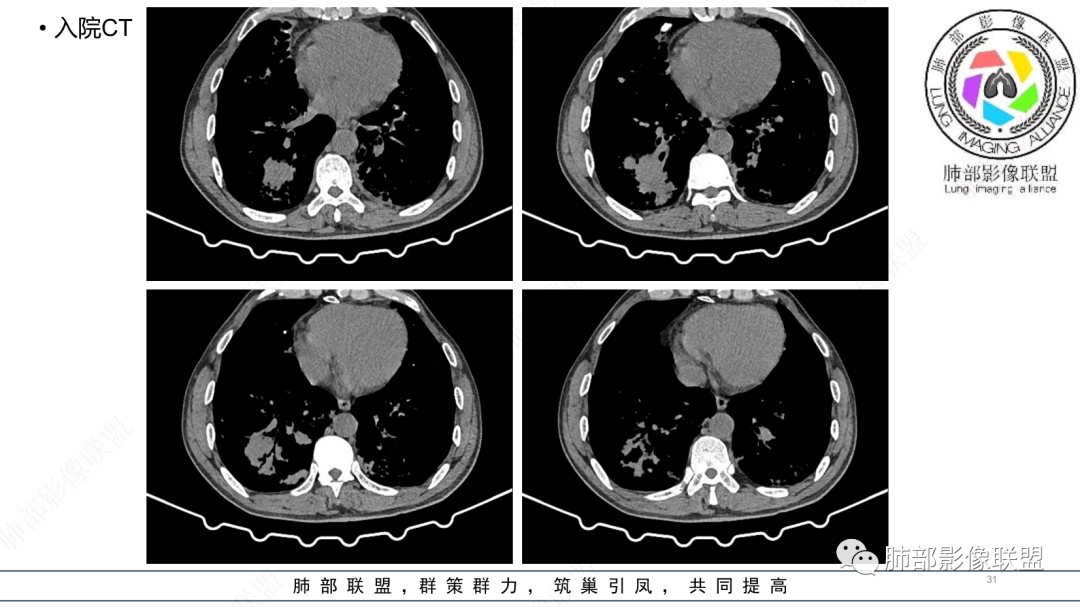

中老年男性,发病一周,发热,炎症指标明显增高,双肺支气管扩张基础,双肺可见多发结节、斑片状、团块状密度增高,边缘尚清。病灶分布与支气管关系密切,考虑支扩合并感染,铜绿,NTM、奴卡、曲霉等,环卫工人,可能接触腐败物较多,考虑曲霉可能大,鉴别奴卡。

男性,56岁,清洁工,临床表现咳嗽咳痰发热。胸部影像:两肺散在斑片、结节及实变影,大部分沿气道分布,以下肺为著并伴发多发支气管扩张及囊腔影,实验室检查白细胞增高,考虑感染性病变,曲霉、铜绿及NTM。

56岁,工作性质:环卫工人。主诉:咳、痰、喘、发病一周。急性起病(或者慢病+AE),呼吸道感染症状。化验指标白细胞、中性、CRP明显升高。影像学显示多灶性,有柱状支扩,囊状支扩等结构肺病,责任细菌主要考虑铜绿假单胞菌,不排除合并其他细菌以阴杆为主;存在树芽影,发热,炎症沿支气管束分布,是否合并TB?真菌?;树芽伴发热支原体感染也要需要考虑进去;全肺多灶性炎症,部分病灶周围有晕,右上叶疑似反晕,内部疑似有丝,右下肺考虑存在粘液栓,加之环卫工工作性质,考虑霉菌,主要考虑曲霉。

影像改变为支扩伴气道来源感染,部分实变性伴有小脓肿及钙化,结合PCT及白细胞、中性粒明显增高,符合细菌感染,首先考虑奴卡,绿脓次之,因为临床有喘息、影像实变性有钙化,加上环卫工这一职业史,需要鉴别曲霉或奴卡合并曲霉。

CT:双肺延支气管血管束分布斑片状、团块状、树芽状密度增高影,部分边界模糊,支气管扩张、部分管壁增厚。考虑气道吸入细菌性感染,铜绿假单孢?